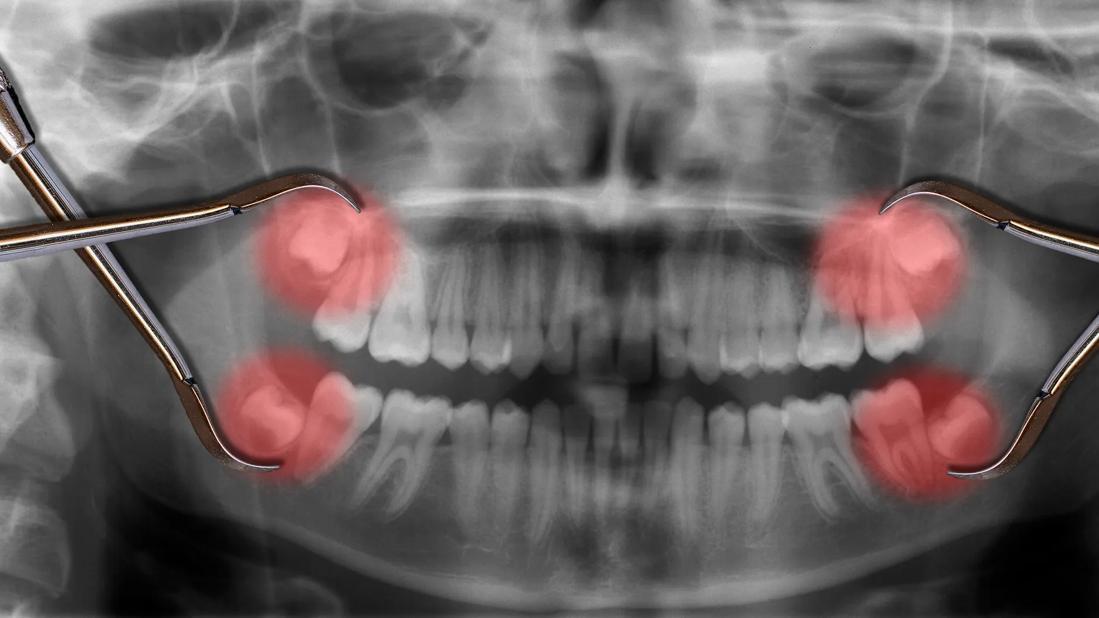

Gum tissue often becomes sensitive, swollen and inflamed around impacted wisdom teeth. Impacted wisdom teeth are essentially trapped in your gums or jawbone. Teeth that are partially or completely buried instead of fully erupted often lead to oral health problems.

“You can’t clean impacted wisdom teeth properly, so they can start to decay and you can develop cavities and gum disease,” says Dr. Janowicz. “Cysts or tumors can also develop around impacted teeth, too.”

Impacted wisdom teeth are common and affect about 90% of people with wisdom teeth. Dentists generally evaluate impacted teeth on a case-by-case basis to determine whether to recommend removal.